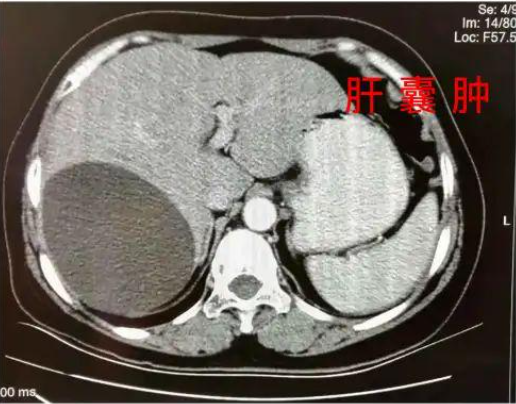

大学毕业后,通过打拼,条件改善了,但是由于身体基础差,又患上了肝囊肿,卵巢囊肿等疾病。工作时候,由于过于拼命,多次晕倒被120抢救!

当她为自己调理了半年后,去体检,医生告诉她可以把药都停了。当时医生都不相信坚持结果,把护士喊来反复确认了好几次!